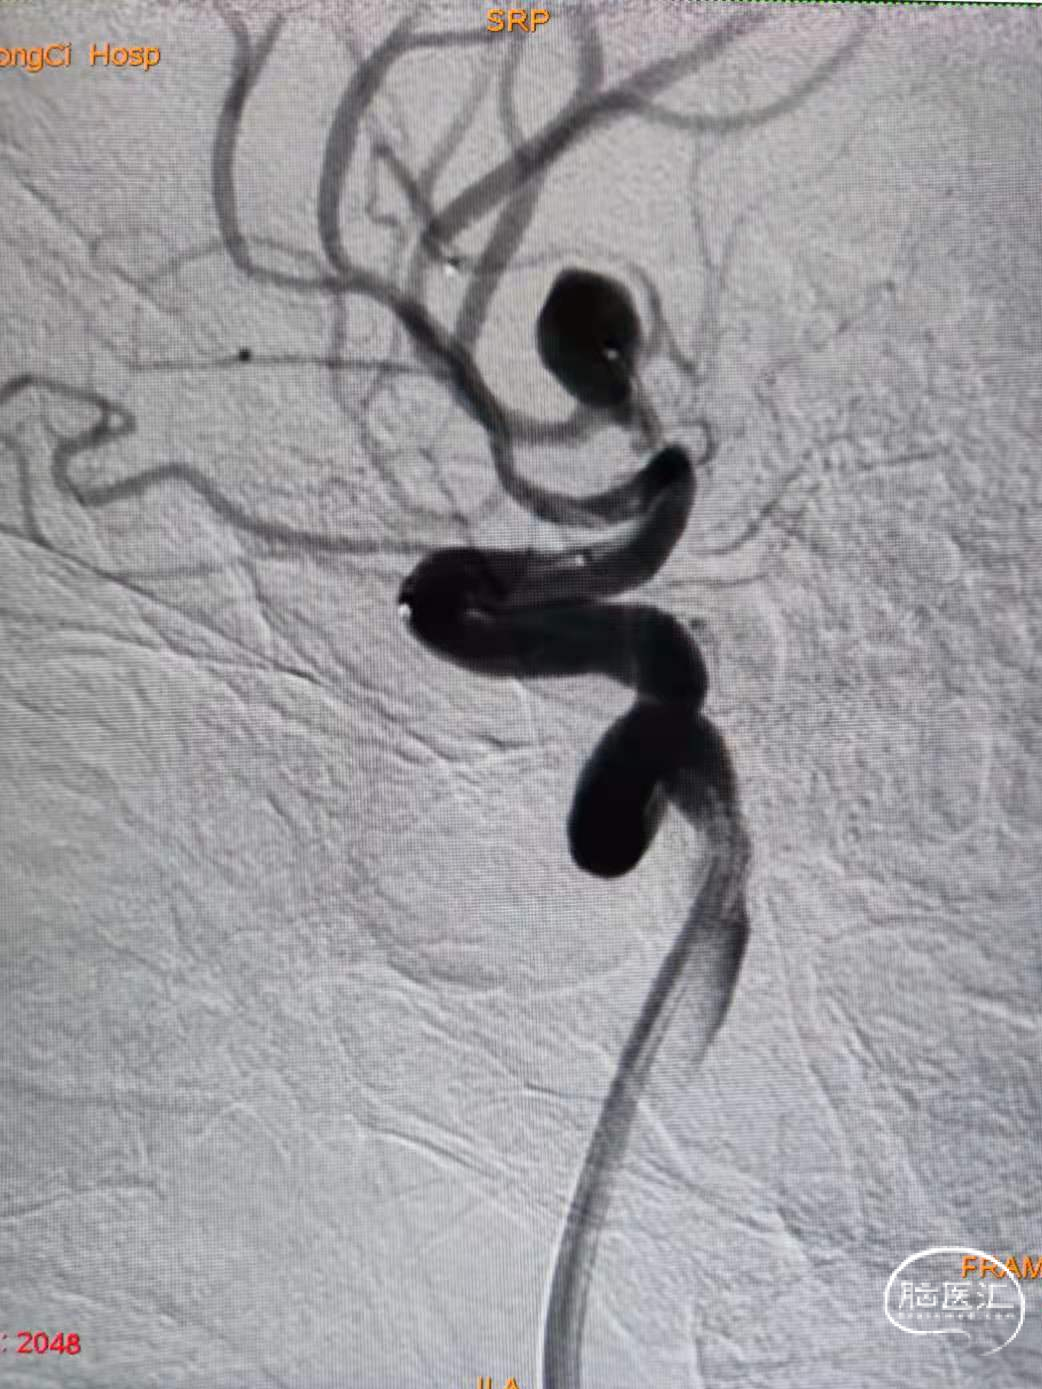

使用SL-10微导管和7*30弹簧圈。成篮满意后释放Atlas 3.0*15支架。支架释放并打开顺利,随后将支架导管穿网眼送入动脉瘤腔内。

3、随后经送入动脉瘤腔内的微导管连续推送6*20、5*20,4*12、3*8、2*6、2*4弹簧圈。后造影显示动脉瘤栓塞满意,上下支干通畅,显影良好。

1、Atlas支架在小直径血管的表现良好,在本例动脉瘤的到位以及在仅1.0mm的上支干血管内打开顺利,为后续的栓塞治疗提供可靠的保证。

2、作为开环小径支架,Atlas轻松穿网孔性能,为单微管技术的使用提供可靠保障。